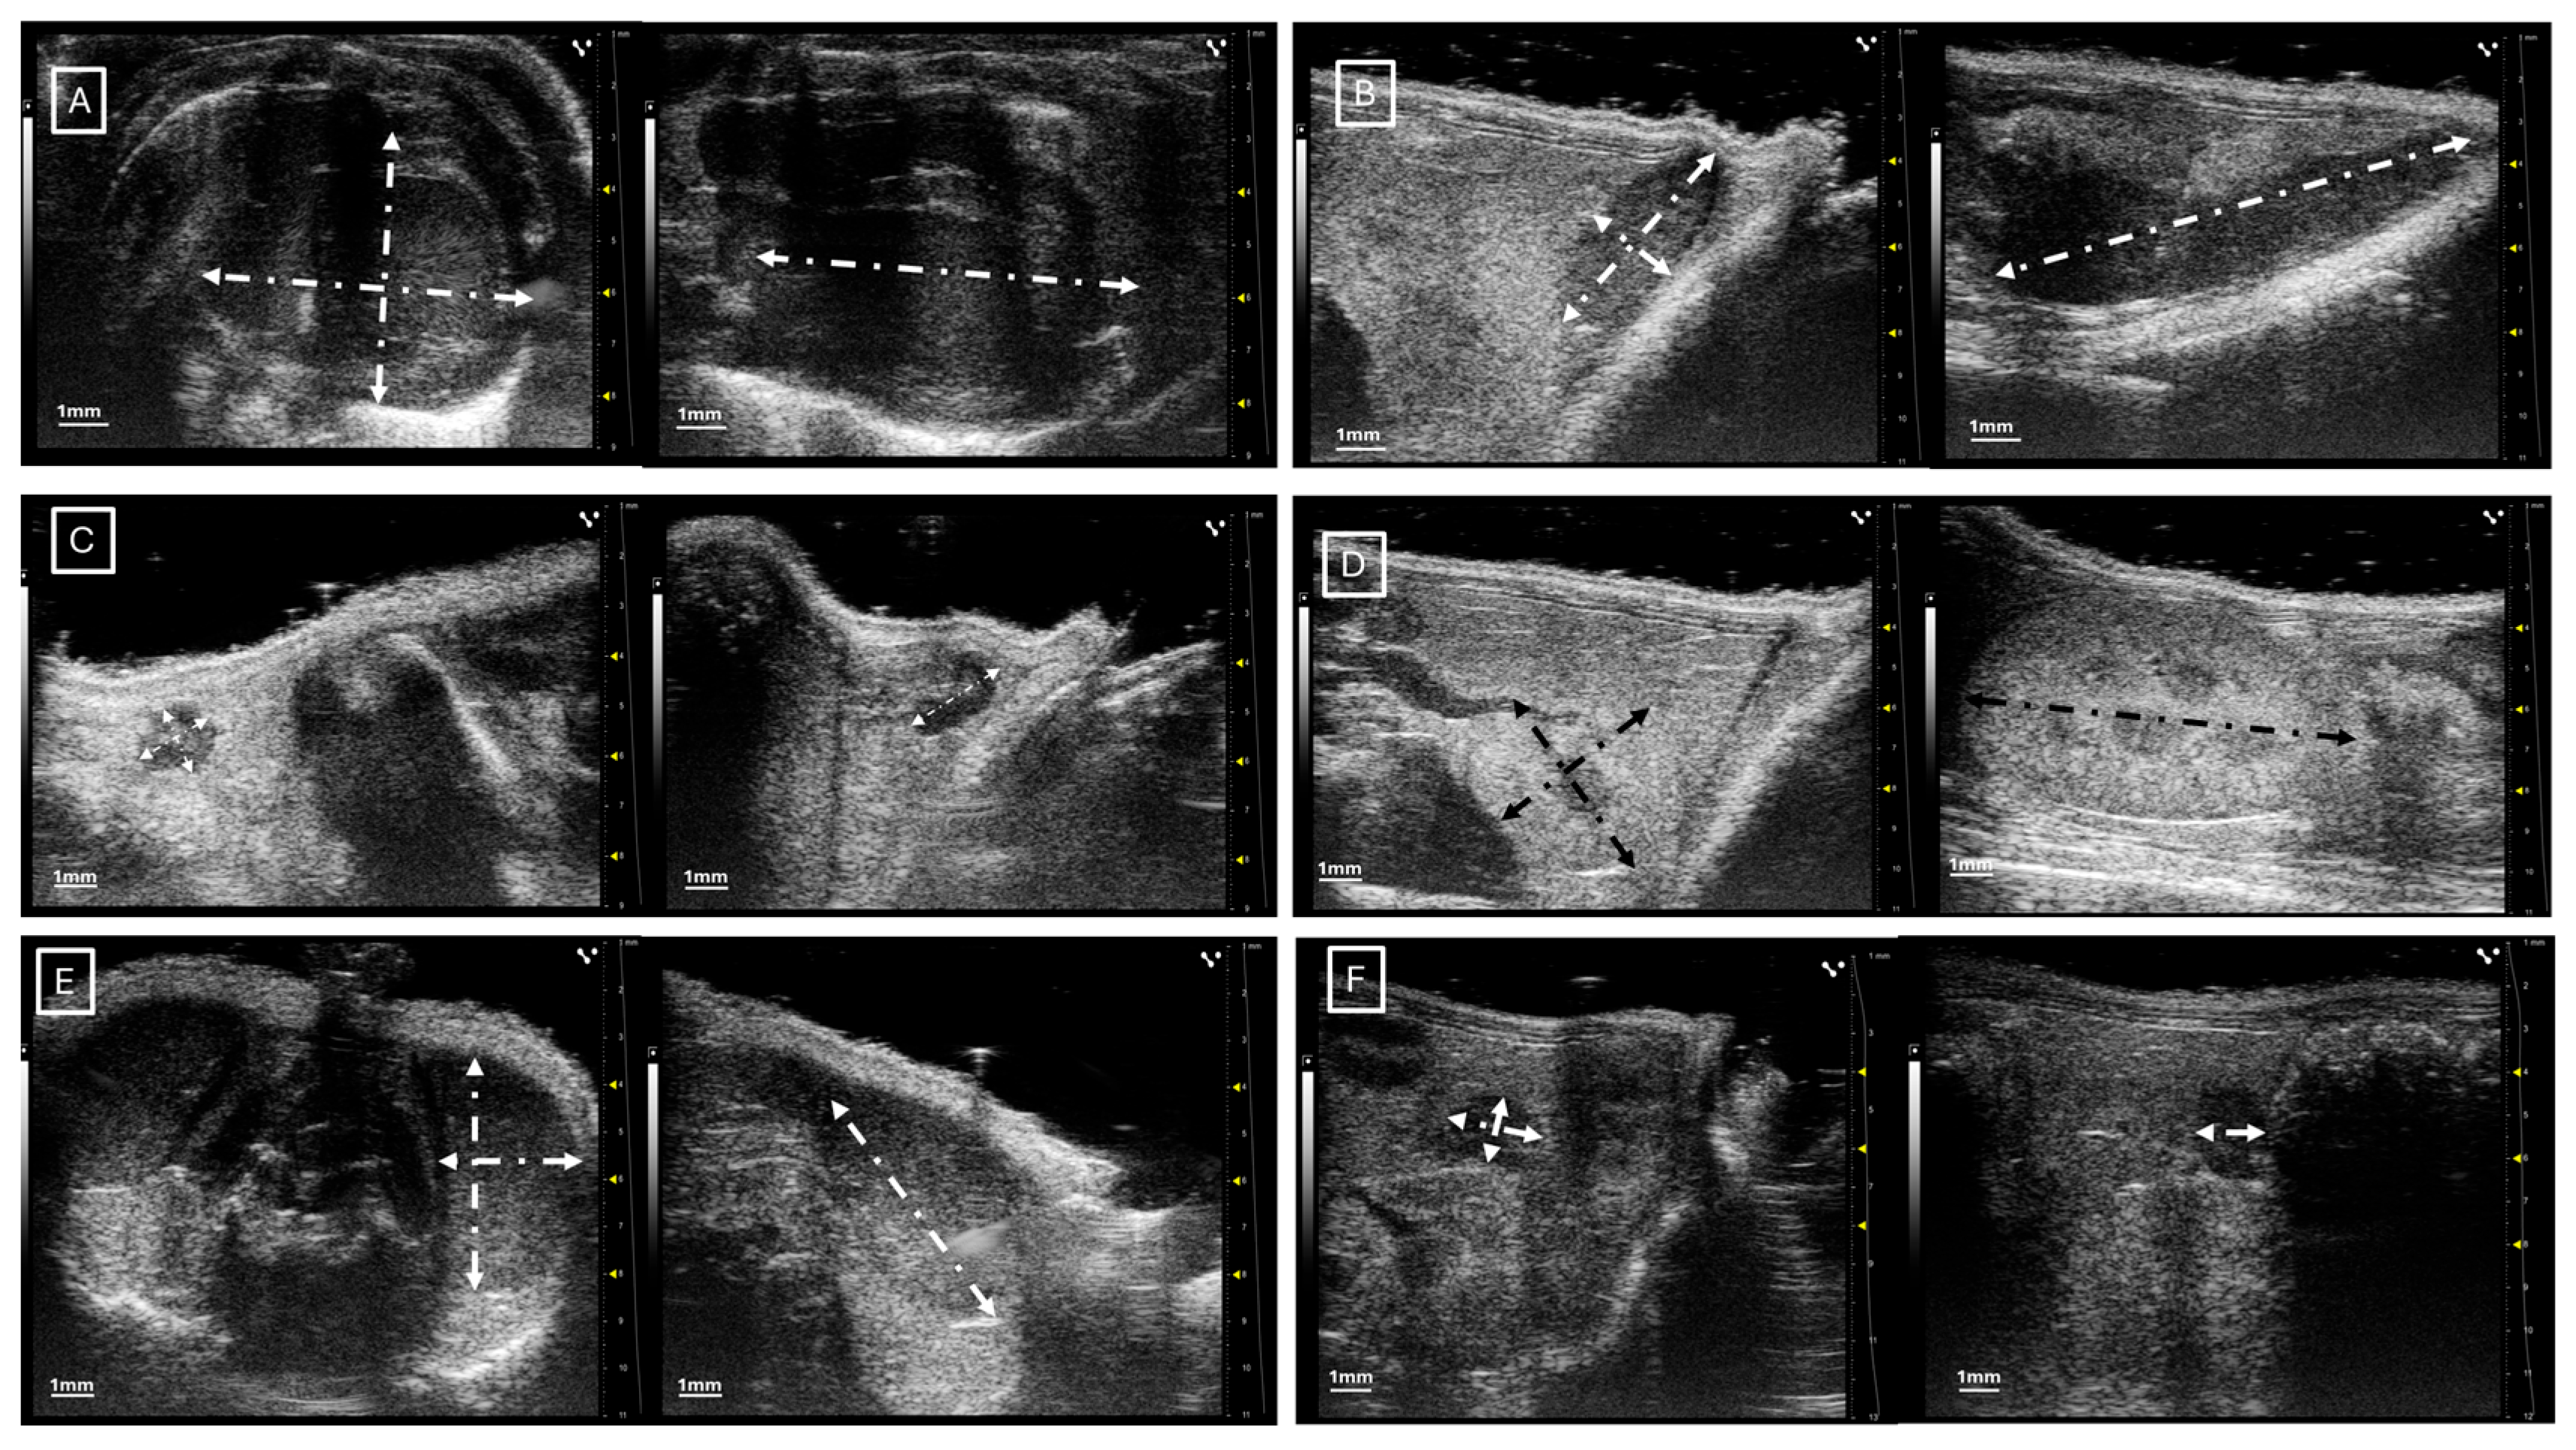

Figure 1 and Figure 2 show examples of ultrasound and microCT diameter measurements. Figure 3 shows examples of manual segmentation.

Figure 1.

Representative images of ultrasound diameter measurements in (A) heart in axial (left) and longitudinal (right) views, (B) spleen in axial (left) and longitudinal (right) views, (C) inguinal lymph nodes in axial (left) and longitudinal (right) views, (D) left kidney in axial (left) and longitudinal (right) views, (E) left testicle in axial (left) and longitudinal (right) views, and (F) left ovary in axial (left) and longitudinal (right) views. In all cases, the diameters are marked with dotted, white, or black lines.